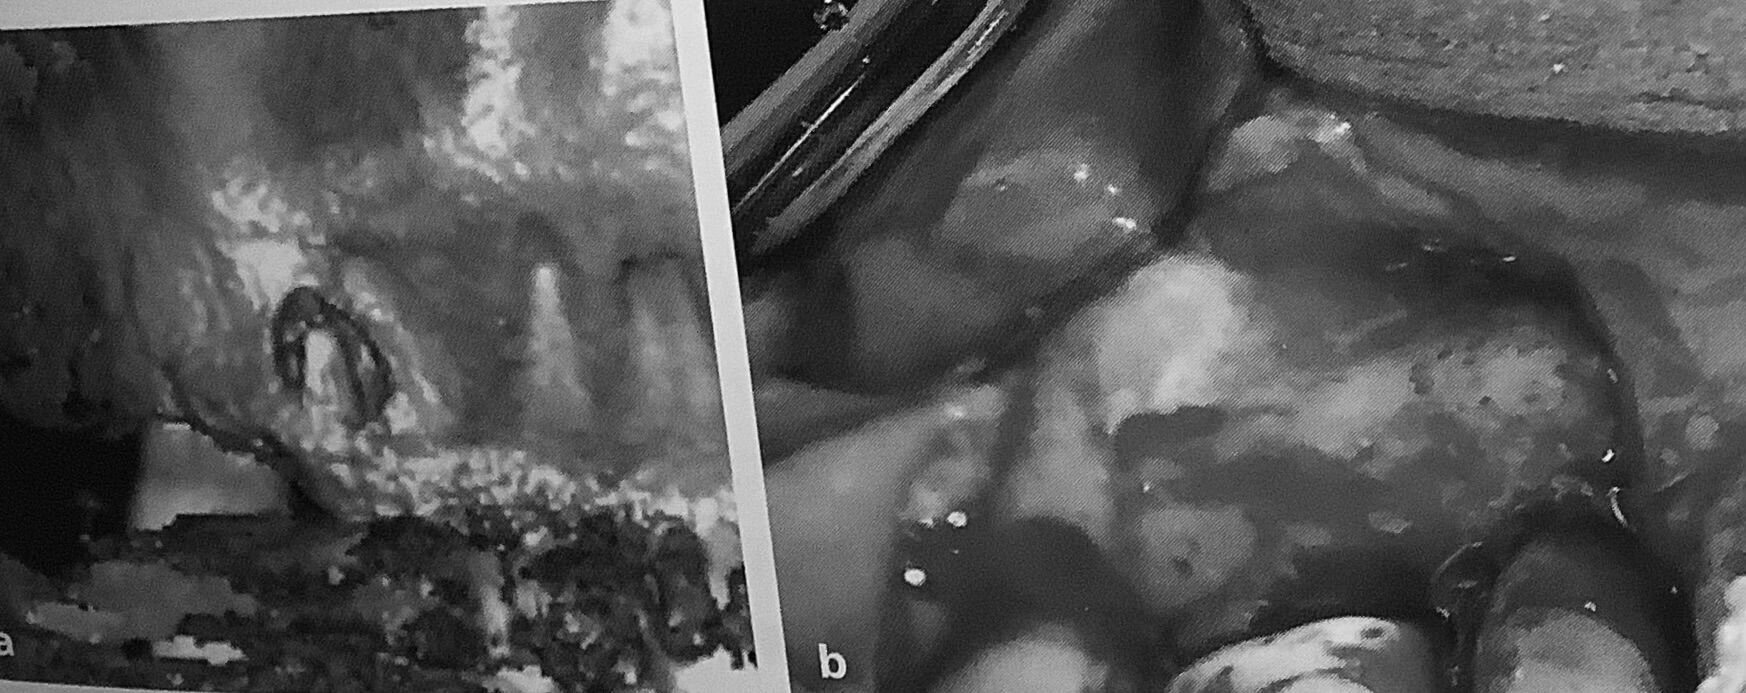

しかしCBCTの特に三次元イメージ画像には、要注意です。

血が出ている絵なんで、

白黒にしました。

左のCTでは根っこの先に穴が開いていて、骨から出ているように見えます。

右は実際の手術の絵で、表面の骨は残っていて根っこの先は見えてません。

もちろん骨の中にまん丸く見えてる病気はあるんですが、

表面の薄い骨などは無いように見えてしいまう事があるんです。